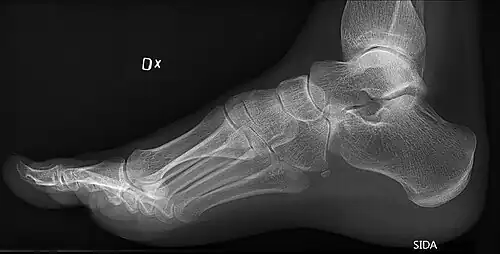

On weightbearing projectional radiography, pes cavus can be diagnosed and graded by several features, the most important being medial peritalar subluxation, increased calcaneal pitch (variable) and abnormal talar-1st metatarsal angle (Meary's angle).[17] Medial peritalar subluxation can be demonstrated by a medially rotated talonavicular coverage angle.[17]

High arch in foot of a person with a hereditary neuropathy